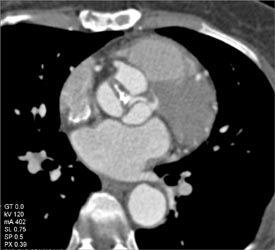

Normal RCA With Multiple Views